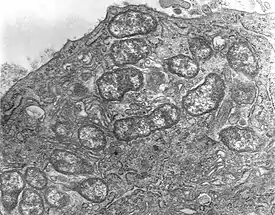

Orientia tsutsugamushi (от яп. ツツガ, tsutsuga — болезнь и ムシ, mushi — насекомое) — вид бактерий из семейства Rickettsiaceae, типовой вид рода ориенций[1] (Orientia)[2]. Возбудитель заболевания, известного как лихорадка цуцугамуши[3]. Является облигатным внутриклеточным паразитом клещей, принадлежащих к семейству Trombiculidae[4][5]. Эндемик так называемого «треугольника цуцугамуши», региона, охватывающего Дальний Восток на севере, Японию на востоке, северную Австралию на юге и Афганистан на западе. Впервые описана Наосуке Хаяси в 1920 году под названием Theileria tsutsugamushi, но в 1995 году переименована в Orientia tsutsugamushi.